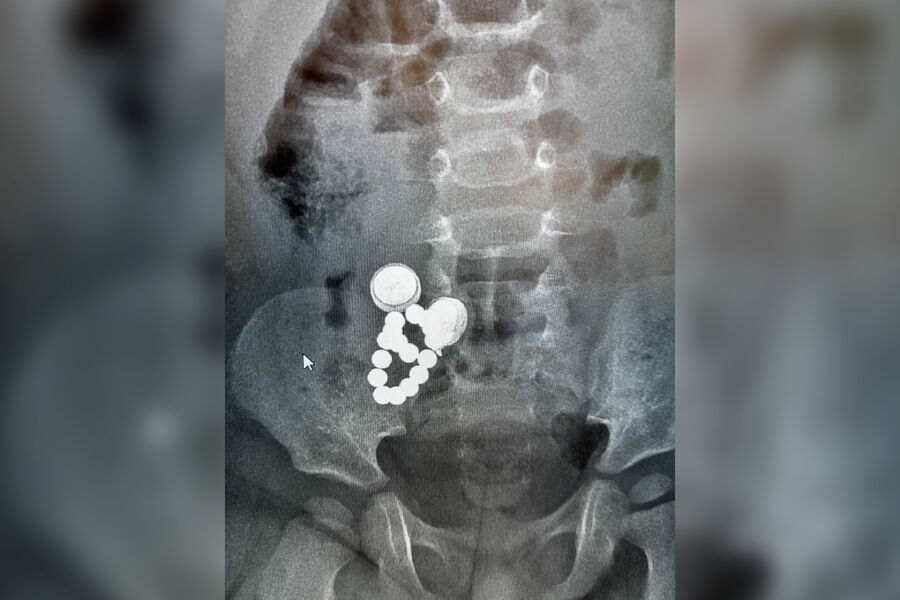

Ребенок в возрасте 1 год и 8 месяцев был госпитализирован с желудочно-кишечным кровотечением в областной центр из Дубровенской районной больницы 13 мая. При диагностике врачи выявили, что в организме у ребенка находится более 15 инородных предметов, а именно 2 батарейки, 16 магнитов и шуруп.